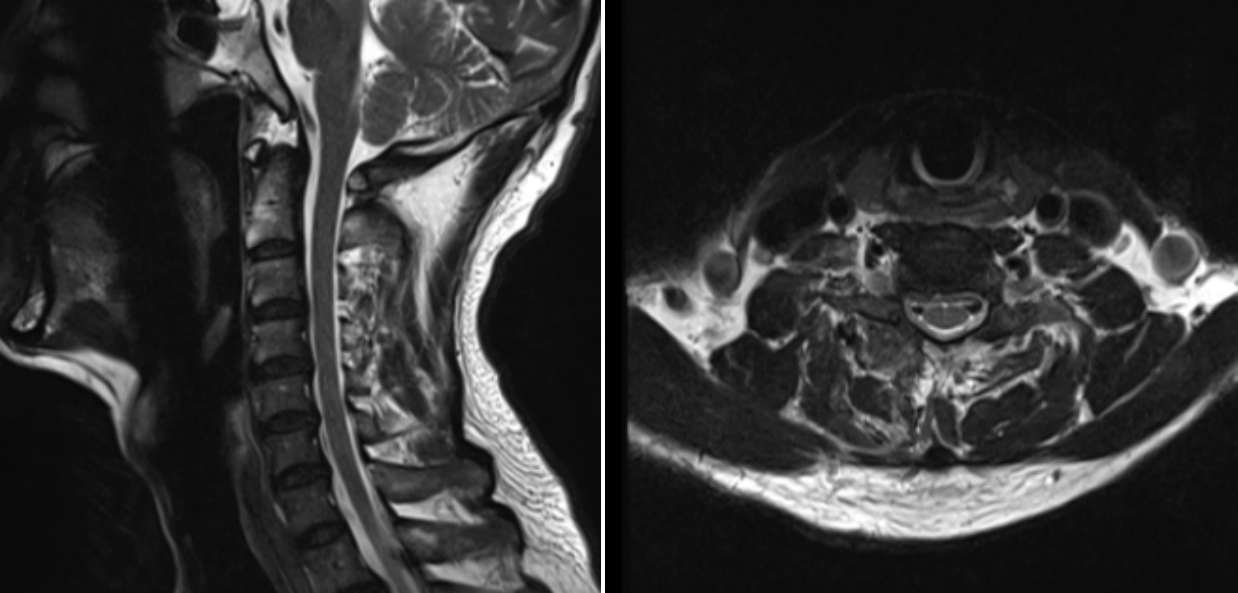

術后效果立竿見影,患者的疼痛癥狀得到了顯著緩解,麻木感也逐漸消退。術后1天,患者便能在醫(yī)護人員的指導下下床活動。經(jīng)過3天的觀察與護理,患者身體狀況良好,順利出院,手術取得圓滿成功。

術后第一天MRI圖像